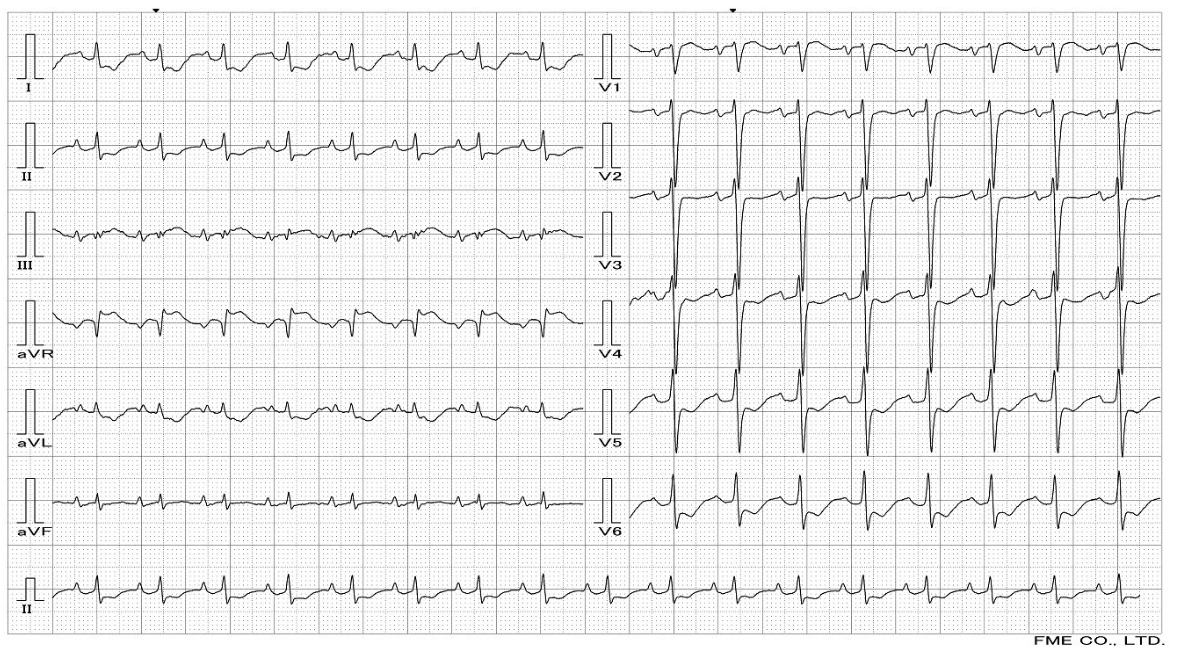

Relevant Test Results Prior to Catheterization

Her ECG demonstrated ST depressions and T wave inversions in leads V2-V6, I, II, aVL, and aVF, indicating myocardial ischemia, potentially secondary to hypoxia and coronary artery disease. Laboratory results showed elevated Troponin I at 1.55 ng/mL and NT-proBNP at 7310 pg/mL, consistent with acute decompensated heart failure.